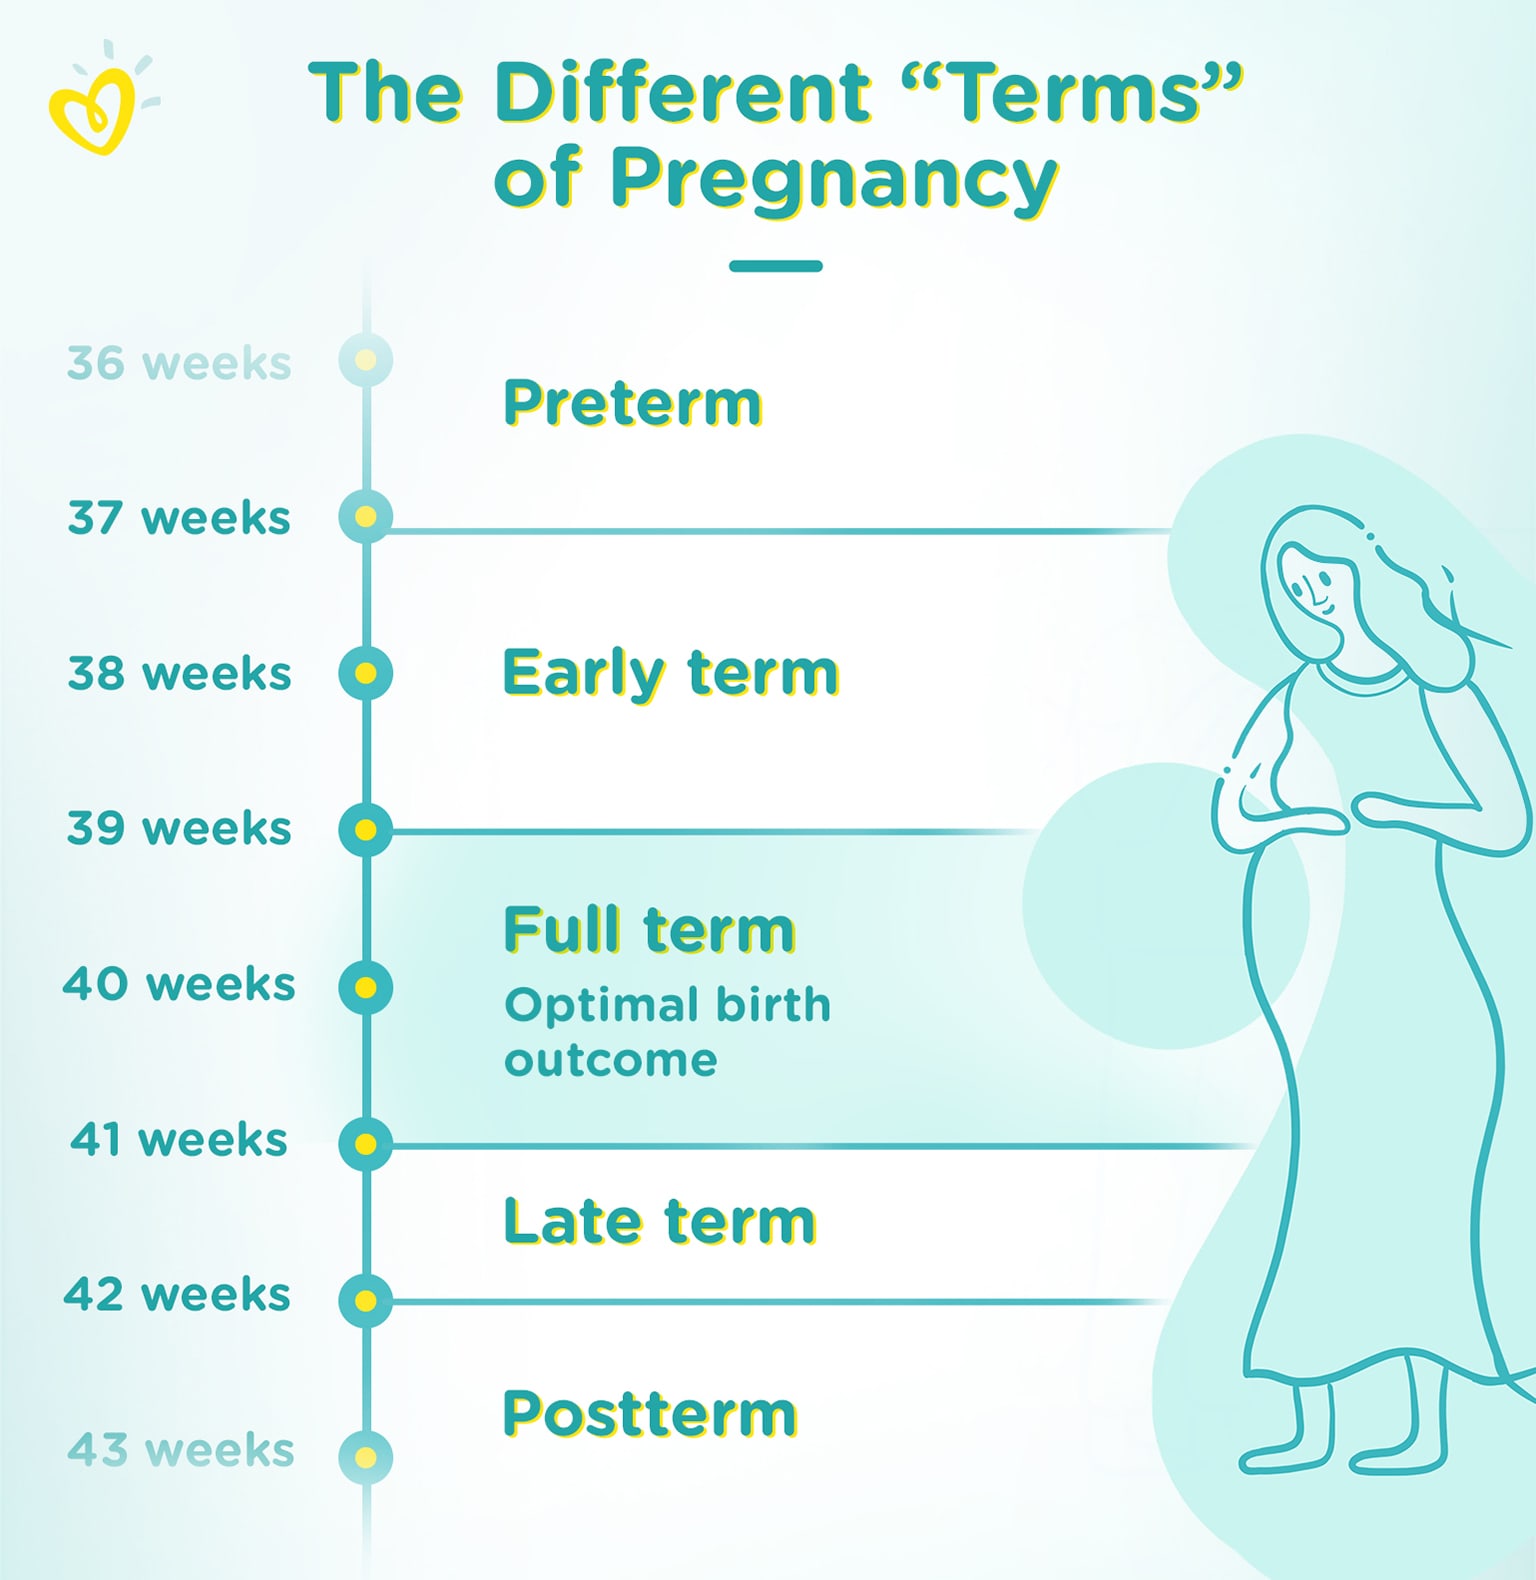

Full-Term Pregnancy Explained | Pampers